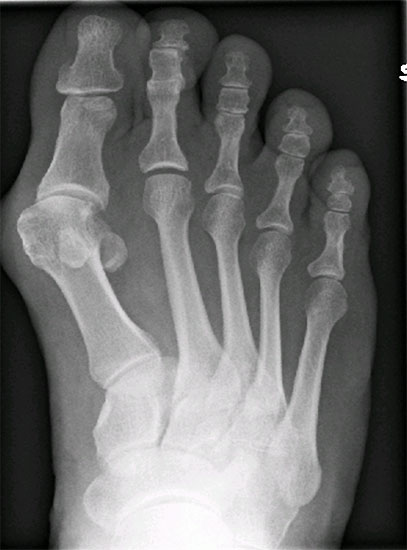

Wenn durch das Anspannen der Muskulatur der 1. Strahl zu einem starren Hebel wird und aussteift, empfehlen wir auf die Durchführung einer TMT-I-Arthrodese zu verzichten und z.B. eine proximale Korrekturosteotomie durchzuführen. So ist nach unserer Auffassung bei jeglicher Dorsalbewegung des 1. Strahles (Instabilität) trotz Anspannung der Peronealmuskulatur (wie beschrieben) die Indikation zur Lapidusarthrodese unabhängig vom Intermetatarsalwinkel gegeben. Bei der Beurteilung des a.p.-Röntgenbildes unter Belastungsbedingungen dient die Bestimmung des Hallux valgus interphalangeus-Winkes und des distalen Artikulationswinkels ggf. zur Indizierung einer additiven Akin-Osteotomie (Abb. 4). Die Stellung des proximalen Artikulationswinkels legt im Falle einer bereits praeoperativ bestehenden Vergrößerung nach Korrektur des Intermetatarsalwinkels eine Korrektur durch eine Reverdin-Green-Laird-Osteotomie nahe (Abb. 5). Die Größe des Intermetatarsalwinkels I/II beeinflusst je nach Größe bei stabilem 1. Strahl die Wahl des jeweiligen Operationsverfahrens.

Im Falle einer Insuffizienz des 1. Strahles wird in jedem Falle eine TMT-I-Arthrodese indiziert sein, hier dient der Intermetatarsalwinkel planerischen Aspekten im Sinne des Ausmaßes der Korrektur am Os cuneiforme I. Die Bestimmung des Metatarsus adductus-Winkels dient der Detektion eines Pes adductus. Im Falle des Vorliegens einer solchen Deformität sind ggf. auch Korrekturosteotomien an den kleineren Metatarsalia zu erwägen, um ausreichend Platz für die Einstellung des Metatarsale I in die Rectusposition zu erhalten. Ein weiteres wichtiges Kriterium in der a.p.-Projektion stellt das Längenverhältnis von Metatarsale I zu Metatarsale II dar, da bei der Durchführung der TMT-I-Arthrodese das Vorliegen einer Minusvariante häufiger die Gefahr einer postoperativen Transfermetatarsalgie birgt und hier unter Umständen über Modifikationen des operativen Vorgehens nachgedacht werden sollte. Hier besteht die Möglichkeit von alternativen Präparationsverfahren im TMT I oder aber der Durchführung einer Interpositionsarthrodese des TMT I zur Verlängerung des 1. Strahles. Alternativ können auch Verkürzungsosteotomien des 2. und 3. Strahles erwogen werden. Als indirekte radiologische Zeichen einer Insuffizienz des 1. Strahles kann ein Klaffen des Spaltes zwischen dem Os cuneiforme mediale und dem Os cuneiforme intermedium sowie eine Hypertrophie der Corticalaes des Metatarsale II gedeutet werden (Abb. 6).